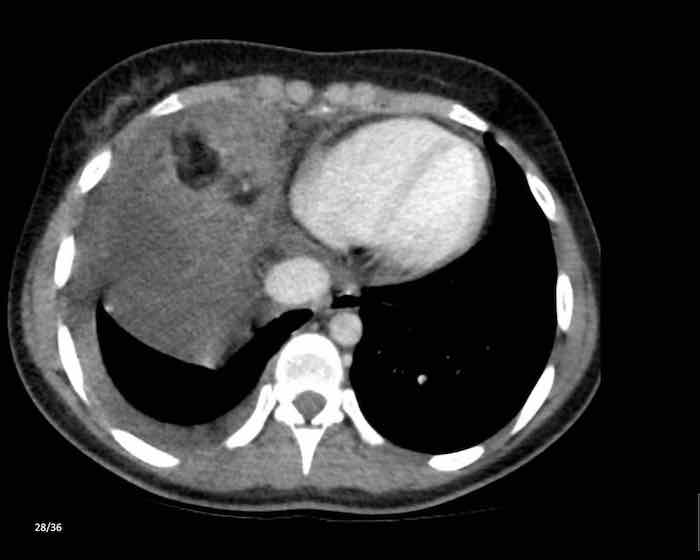

Các hình ảnh này của một nam giới 71 tuổi.

Trên CT ngực, tình cờ phát hiện một khối ở tuyến ức.

Hãy phân tích các hình ảnh. Nhận định của bạn là gì?

Hình ảnh

Một phần tổn thương có ngấm thuốc cản quang và có một số vôi hóa, có thể nằm ở thành nang.

Khi một tổn thương tuyến ức có thành phần đặc, nguyên tắc là… “khi còn nghi ngờ, hãy phẫu thuật cắt bỏ”.

Tổn thương đã được phẫu thuật cắt bỏ dựa trên kết quả CT và kết quả giải phẫu bệnh cho thấy đây là u tuyến ức dạng nang.